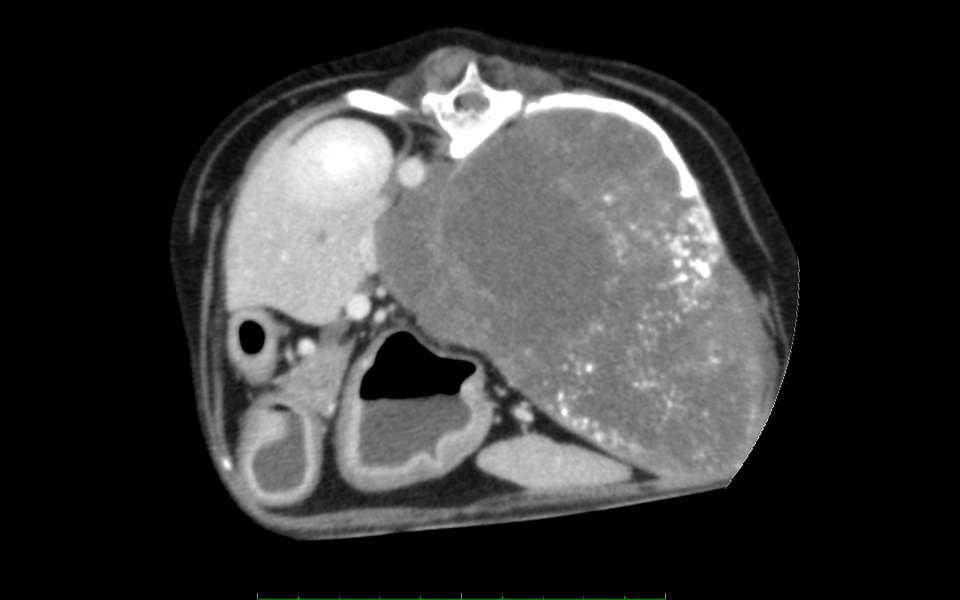

下記の画像は当院で撮影した肋骨腫瘍の症例のCT画像です。超音波検査では腫瘤が巨大すぎて発生源の特定が困難でしたが、CT検査を実施し肋骨の発生源の特定、大きさ、他の臓器の浸潤度合いなど判断することができました。

この子は肋骨3本ごと切除する手術にも耐えてくれて手術も無事成功し今は元気に過ごしております。